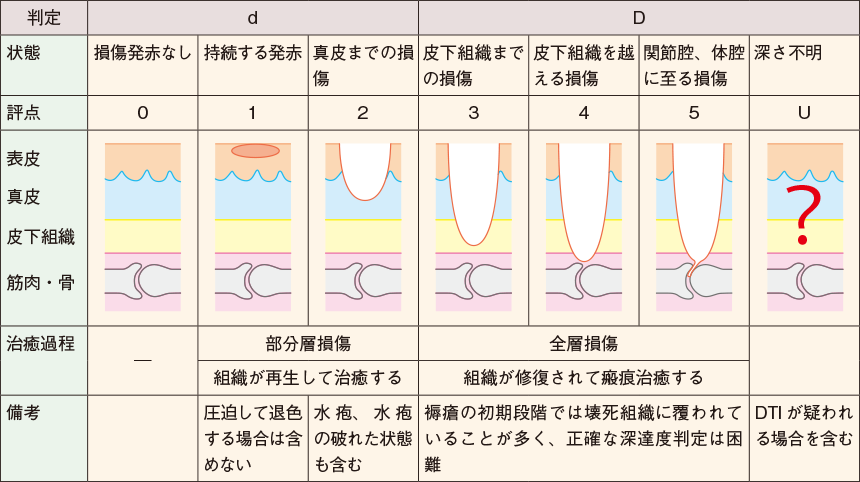

看護師のための褥瘡評価の完全ガイドDESIGN-R評価 - しごとレトリバーガイド。

特集2 DESIGN-R®2020について花王ハイジーンソルーション。

特集2 DESIGN-R®2020について花王ハイジーンソルーション。

特集2 DESIGN-R®2020について花王ハイジーンソルーション。

特集2 DESIGN-R®2020について花王ハイジーンソルーション。

褥瘡の評価 DESIGN-R デザインアール を用いた評価のコツナース専科。

褥瘡評価スケールの種類とDESIGN-R®2020による評価方法 医療従事者対象ネスレ栄養ネット。

褥瘡の評価 DESIGN-R デザインアール を用いた評価のコツナース専科。

看護師のための褥瘡評価の完全ガイドDESIGN-R評価 - しごとレトリバーガイド。